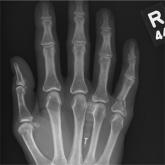

A 48-year-old woman presents to the urgent care center with complaints of right hand pain second-ary to an injury she sustained earlier in the day. He...